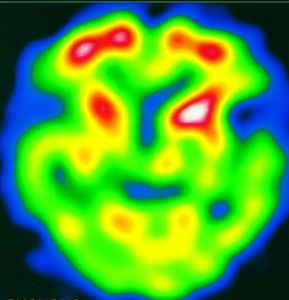

ECT(emission computed tomography),即辐射断层成像,其成像原理主要依据的是进入人体循环系统的示踪分子,会根据不同成分在不同组织的聚集浓度的不同而呈现出人体不同组织活性强度的差异。所以,我们一般称之为功能性成像(functional imaging)。

对于癌症,早起的癌细胞不会导致组织上明显的差异,所以CT很难显示出来,而ECT则可以通过查看细胞活性的差异来进行癌症的早期诊断,故效果较好(癌细胞的活性一般比普通细胞和组织要高很多)。此外,通过使用ECT对于心肌活性的诊断、脑组织活性的诊断,可以判断是否心肌缺血,冠心病、帕金森等疾病,所以ECT对于这些疾病的早期诊断会有一些优势。